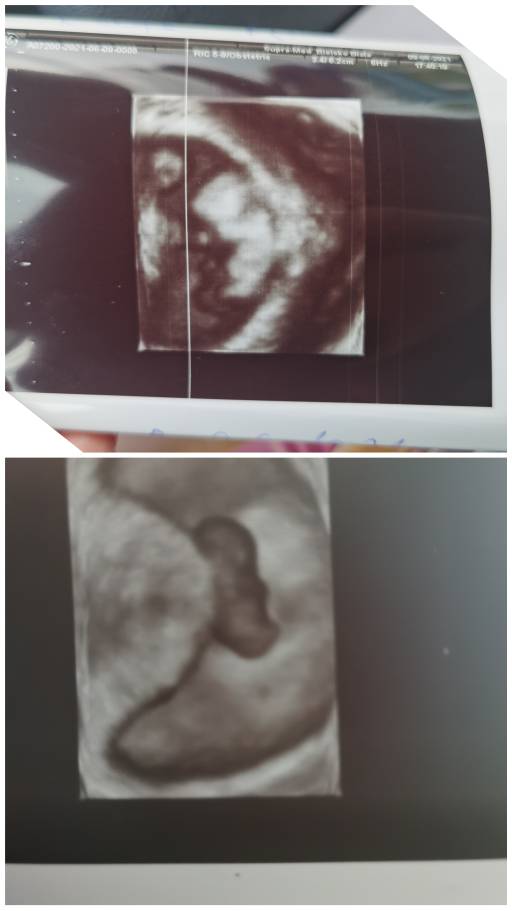

Cześć dziewczyny. Witam się z Wami. Jestem w trzeciej ciąży. Na początku było dużo obaw, nadal są, ale im ciąża wyższa tym ma się więcej nadziei, że będzie wszystko ok. Jestem mamą dwóch chłopców, teraz trzecia ciąża i zastanawiam się czy w brzuszku mieszka trzeci chłopczyk, czy może dziewczynka. Dzisiaj porównywałam sobie układ dzieci w brzuszku i zastanawiam się czy on może mieć wpływ na płeć. Zobaczcie same. Trzeci bobo też ma taki sam uklad, czyli główka z lewej strony, pupka z prawej. Mamy które mają kolejną ciążę może podpowiecie czy u Was się to sprawdziło. Czekam na moją upragnioną perełkę, chociaż to dopiero 10 tydzień to już się jej nie mogę doczekać. Pozdrawiam Was mamusie [emoji4]

Hej ja właśnie porownalam zdjęcia z tego samego okresu mniej więcej.. Na pierwszym są trzy ciąże, pierwsza od góry, obecnie a dwie pozostałe to moje córeczki, na drugim zdjęciu na górze obecnie na dole jedna córka.. Chyba ułożenie jest odwrotne ale nie wiem czy teoria się sprawdzi i będzie inna płec [emoji6] mam 3 córki i oczywiście gdyby był syn to byłoby spełnienie marzeń [emoji3590] w każdym bądź razie ja nastawiam się na córeczkę żeby nie mieć jakiegoś zawodu później [emoji6]

CollageMaker_20210615_084816660.jpeg

CollageMaker_20210615_084906247.jpeg